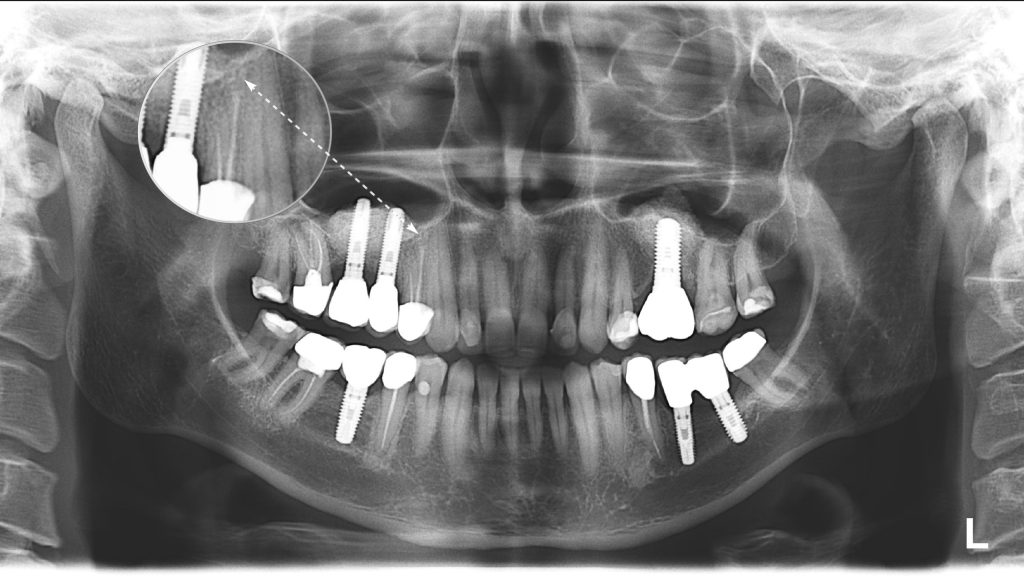

A panoramic dental X-Ray was performed to determine the appropriate treatment. No visible pathology is evident near tooth 14 (Universal 5).

A CBCT scan was performed as part of the checkup, and a radiological screening was created using Diagnocat AI. The report revealed a periapical lesion, which cannot be seen in an ordinary panoramic X-ray.